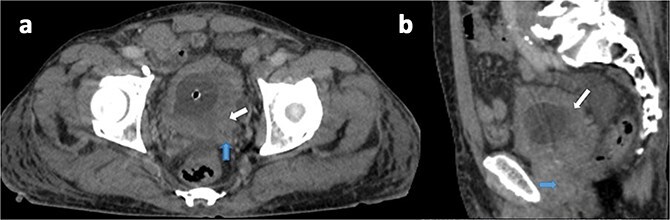

恶性triton肿瘤(MTTs)是一种罕见的恶性周围神经鞘肿瘤亚型,以横纹肌母细胞分化为特征,常与1型神经纤维瘤病(NF-1)相关。原发性膀胱mtt非常罕见,文献记载的病例很少。我们报告一例75岁男性无神经纤维瘤病1型病史的表现血尿和尿路梗阻。影像学显示一个6.5 × 4 × 2 cm的浸润性膀胱肿块,组织病理学证实为高级别梭形细胞肿瘤,伴有双期神经源性(s100阳性)和横纹肌母细胞(desmin和myogenin阳性)分化,符合MTT的诊断。尽管行根治性膀胱前列腺切除术,患者还是死于术后并发症。该病例突出了膀胱MTTs的侵袭性行为、诊断挑战和预后不良,强调了免疫组织化学在将其与其他梭形细胞肿瘤区分开来方面的关键作用。这种罕见的表现强调了进一步研究阐明其发病机制和优化治疗策略的必要性。

Malignant triton tumors (MTTs) are a rare subtype of malignant peripheral nerve sheath tumors characterized by rhabdomyoblastic differentiation, often associated with neurofibromatosis type 1 (NF-1). Primary MTTs of the bladder are exceptionally uncommon, with few documented cases. We report a case of a 75-year-old male without neurofibromatosis type 1 history presenting with hematuria and urinary obstruction. Imaging revealed a 6.5 × 4 × 2 cm invasive bladder mass, and histopathology confirmed a high-grade spindle cell neoplasm with biphasic neurogenic (S100-positive) and rhabdomyoblastic (desmin- and myogenin-positive) differentiation, consistent with a diagnosis of MTT. Despite radical cystoprostatectomy, the patient succumbed to postoperative complications. This case highlights the aggressive behavior, diagnostic challenges, and poor prognosis of bladder MTTs, emphasizing the critical role of immunohistochemistry in distinguishing them from other spindle cell neoplasms. The rarity of this presentation underscores the need for further research to elucidate its pathogenesis and optimize therapeutic strategies.